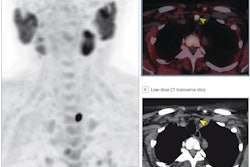

FCH-PET image of an ectopic mediastinal parathyroid adenoma (arrows) on (A) sagittal and (B) axial view fused with simultaneous MRI. This patient had previously undergone a bilateral neck exploration, which had failed to localize a left lower gland. Ultrasound, sestamibi, and 4D CT were all negative. After FCH-PET localization, a robot-assisted left thoracoscopic approach was employed to resect the gland from the aortopulmonary window. Follow-up blood work 8 months after surgery confirmed normalization of calcium. Image courtesy of Surgery.Graves and colleagues found that F-18 FCH-PET localized at least one cancer lesion in 93% of patients overall and in 91% of patients with previously negative imaging, leading to a change in preoperative strategy in 60% of patients. Of 76 patients who underwent parathyroidectomy, 58 (77%) had laboratory data at least six months afterward, with 55 out of 58 of these patients (95%) demonstrating cure.